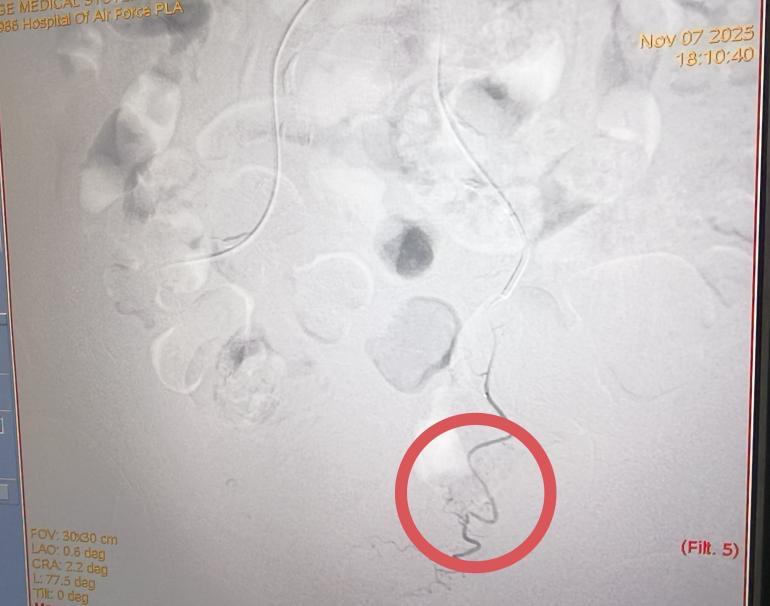

术后

11月7日下午,手术正式进行,全程在患者清醒状态下完成,痛苦小,术后仅需对穿刺点进行加压包扎,恢复迅速。术后第二天,李老先生即可下床活动,身体恢复良好,目前已康复出院。